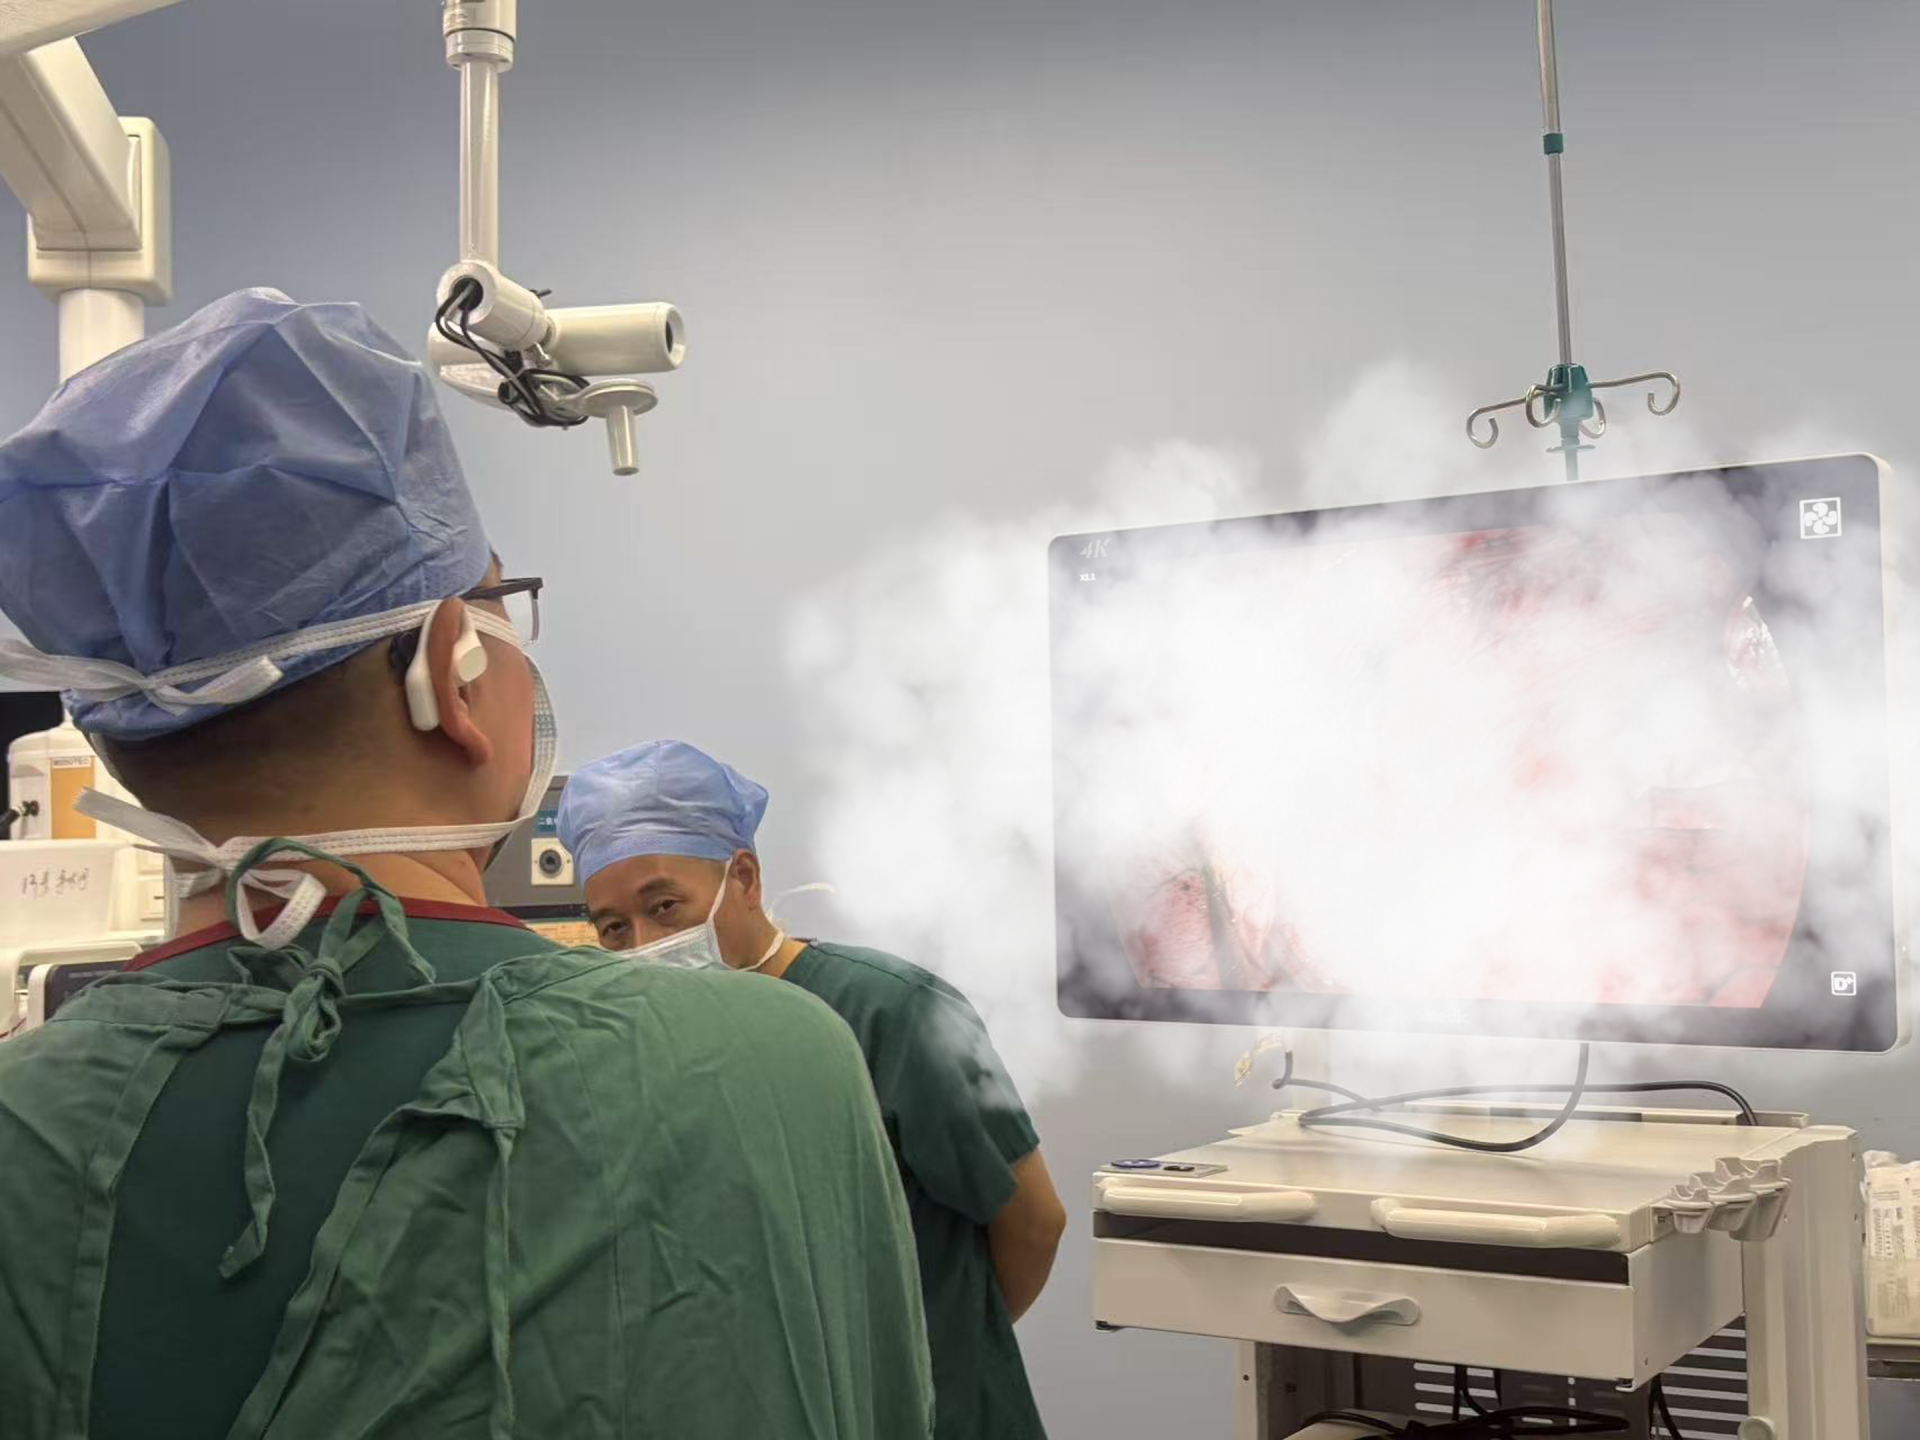

荆楚网(湖北日报网)讯(通讯员 刘敬为 郑威)近来,尖板眼孝感市中心医院胸心外科与呼吸内科联合凭仗先进的医院医疗技能,成功运用 LungPro导航为两名肺结节患者施行精准微创切除手术。精准节危此次手术的定位顺利开展,显示了医院在肺部疾病医治范畴的微创完结杰出实力,也为肺结节患者带来了更精准、肺结安全、尖板眼高效的医院医治新挑选。

孝感市中心医院胸心外科郑威主任表明:“此次运用 LungPro 导航系统成功完结手术,是医院表里联动多学科协作在肺部疾病医治范畴的一次重要打破。该技能的使用明显提高了肺结节手术的精准性与安全性,让更多患者可以获益于微创、高效的医治计划。”。